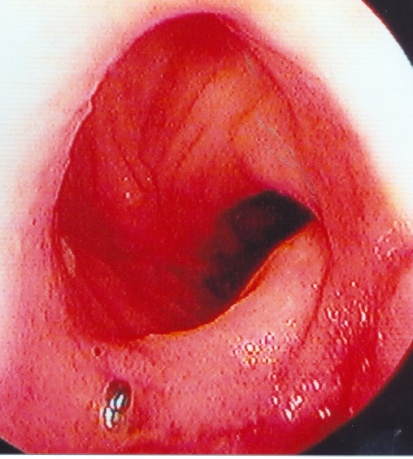

Κολονοσκόπηση. Ευδιάκριτα ευρήματα ισχαιμικής κολίτιδας (Ευγενική παραχώρηση Dr. V. Penopoulos)